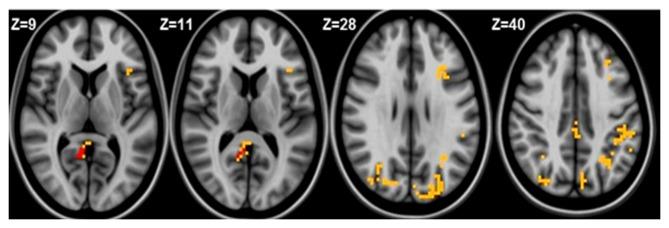

Iron deficiency continues to be the most prevalent micronutrient deficit worldwide. Since iron is involved in several processes including myelination, dopamine neurotransmission and neuronal metabolism, the presence of iron deficiency anemia (IDA) in infancy relates to long-lasting neurofunctional effects. There is scarce data regarding whether these effects would extend to former iron deficient anemic human adults. Resting state functional magnetic resonance imaging (fMRI) is a novel technique to explore patterns of functional connectivity. Default Mode Network (DMN), one of the resting state networks, is deeply involved in memory, social cognition and self-referential processes. The four core regions consistently identified in the DMN are the medial prefrontal cortex, posterior cingulate/retrosplenial cortex and left and right inferior parietal cortex. Therefore to investigate the DMN in former iron deficient anemic adults is a particularly useful approach to elucidate de long term effects on functional brain. We conducted this research to explore the connection between IDA in infancy and altered patterns of resting state brain functional networks in young adults. Resting-state fMRI studies were performed to 31 participants that belong to a follow-up study since infancy. Of them, 14 participants were former iron deficient anemic in infancy and 17 were controls, with mean age of 21.5 years (±1.5) and 54.8% were males. Resting-state fMRI protocol was used and the data was analyzed using the seed based connectivity statistical analysis to assess the DMN. We found that compared to controls, former iron deficient anemic subjects showed posterior DMN decreased connectivity to the left posterior cingulate cortex (PCC), whereas they exhibited increased anterior DMN connectivity to the right PCC. Differences between groups were also apparent in the left medial frontal gyrus, with former iron deficient anemic participants having increased connectivity with areas included in DMN and dorsal attention networks. These preliminary results suggest different patterns of functional connectivity between former iron deficient anemic and control young adults. Indeed, IDA in infancy, a common nutritional problem among human infants, may turn out to be important for understanding the mechanisms of cognitive alterations, common in adulthood.